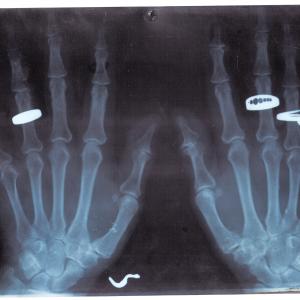

Il recupero di radiografie appartenute a un ortopedico attivo negli anni '80, permettono un'incursione attraverso il tema dell'errore, degli spazi del discorso nell'immagine e dello slittamento del senso.

La dislocazione produce delle opere simili ai rayogrammi di Man Ray o agli equivalenti di Stieglitz, continuando allo stesso tempo a parlarci della pratica vernacolare.